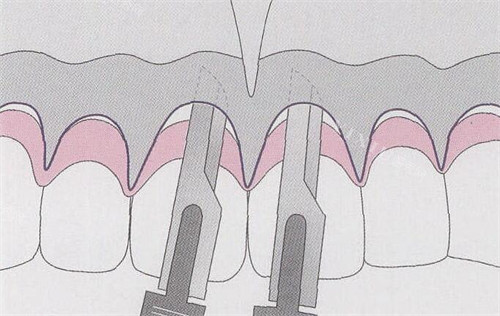

牙冠延长术是解决龈笑露龈问题的关键一步。它就像是技艺娴熟的雕刻师,通过手术的方式,比较准地去除部分牙龈组织和骨组织,从而暴露出更多的牙冠结构。

这一过程需要医生具备高超的技术和丰富的经验,因为要精细控制去除的组织量,既要达到改善牙龈暴露比例的目的,又不能损伤牙齿的根基和周围的健康组织。手术完成后,牙齿的外观会得到显著改善,原本被过多牙龈遮挡的牙冠得以充分展现,为后续的贴面修复打下良好的基础。